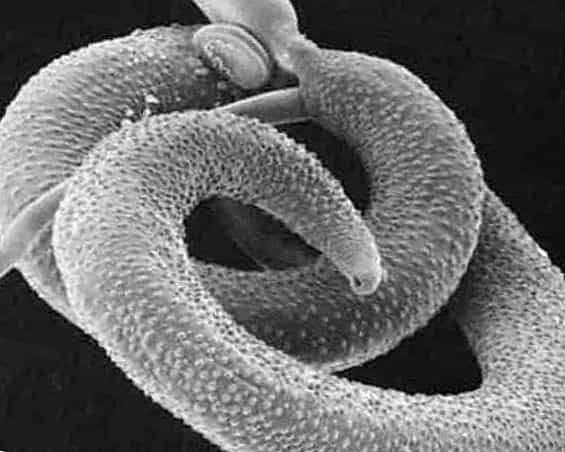

Шистосомоз: что нужно знать о паразитах